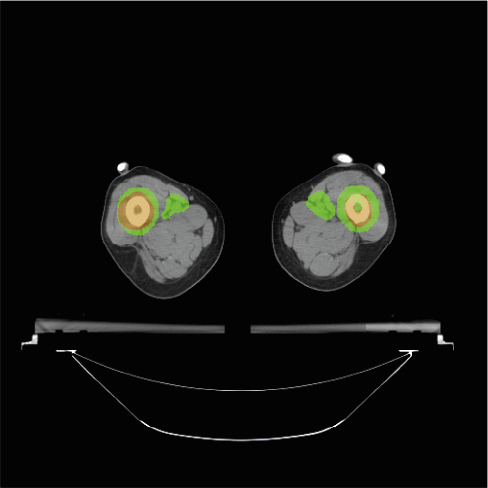

Figure 1 presents an example of the PTV_Tot defined for a patient. The dataset contains the CT scans of each patient and the corresponding PTV_Tot structure stored using the DICOM-RT format. In this study, we trained a model to directly segment the PTV_Tot target. Unlike other PTVs and CTVs, the PTV_Tot is the only target consistently annotated by ROs for all 100 patients included in the dataset.